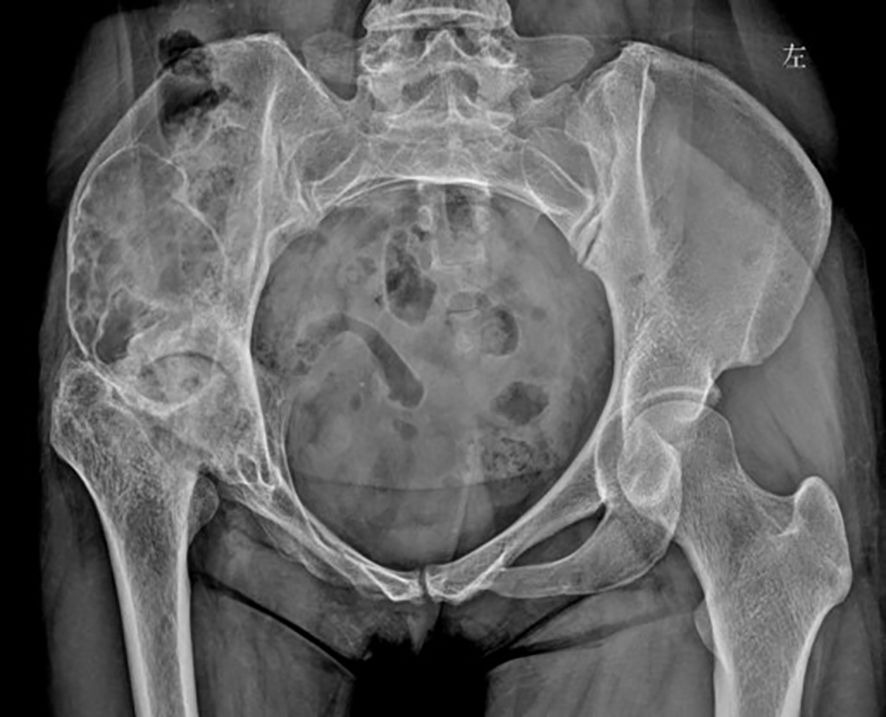

Figure 6

Figure 6. One-year postoperative anteroposterior pelvic radiograph showed good recovery of the right ilium, consistent with postoperative changes.